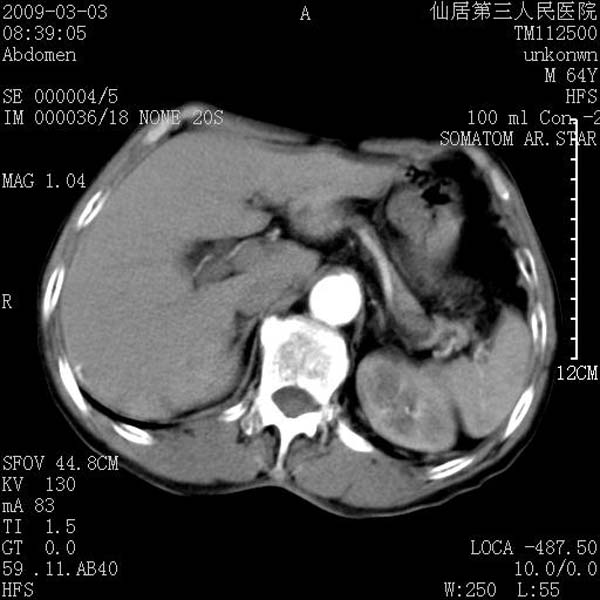

标题: CT18469:男性,64y,体检B超示肝脏低回声肿块,有胃溃疡手术 [打印本页]

标题: CT18469:男性,64y,体检B超示肝脏低回声肿块,有胃溃疡手术

患者,男性,64y,体检b超示肝脏低回声肿块,有胃溃疡手术史。